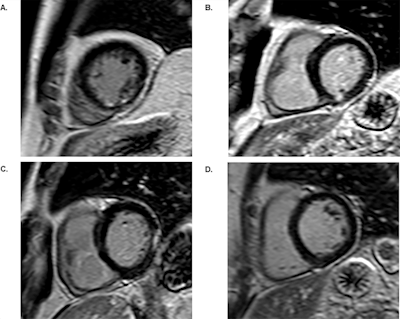

Previous research had investigated the two-year prognosis of these patients using late gadolinium enhancement (LGE) cardiac MRI; however, the long-term risk had not been explored, according to the researchers. Therefore, they conducted a prospective, multicenter study of 235 patients who had undergone LGE cardiac MRI and coronary angiography between January 2008 and March 2011 for suspected stable coronary artery disease. The subjects had no indications of a previous heart attack.

Two radiologists separately reviewed the cardiac MR images for areas of late gadolinium enhancement in more than one imaging plane to indicate an unrecognized myocardial infarction, while two readers unaware of the LGE cardiac MRI results interpreted all coronary angiographies.